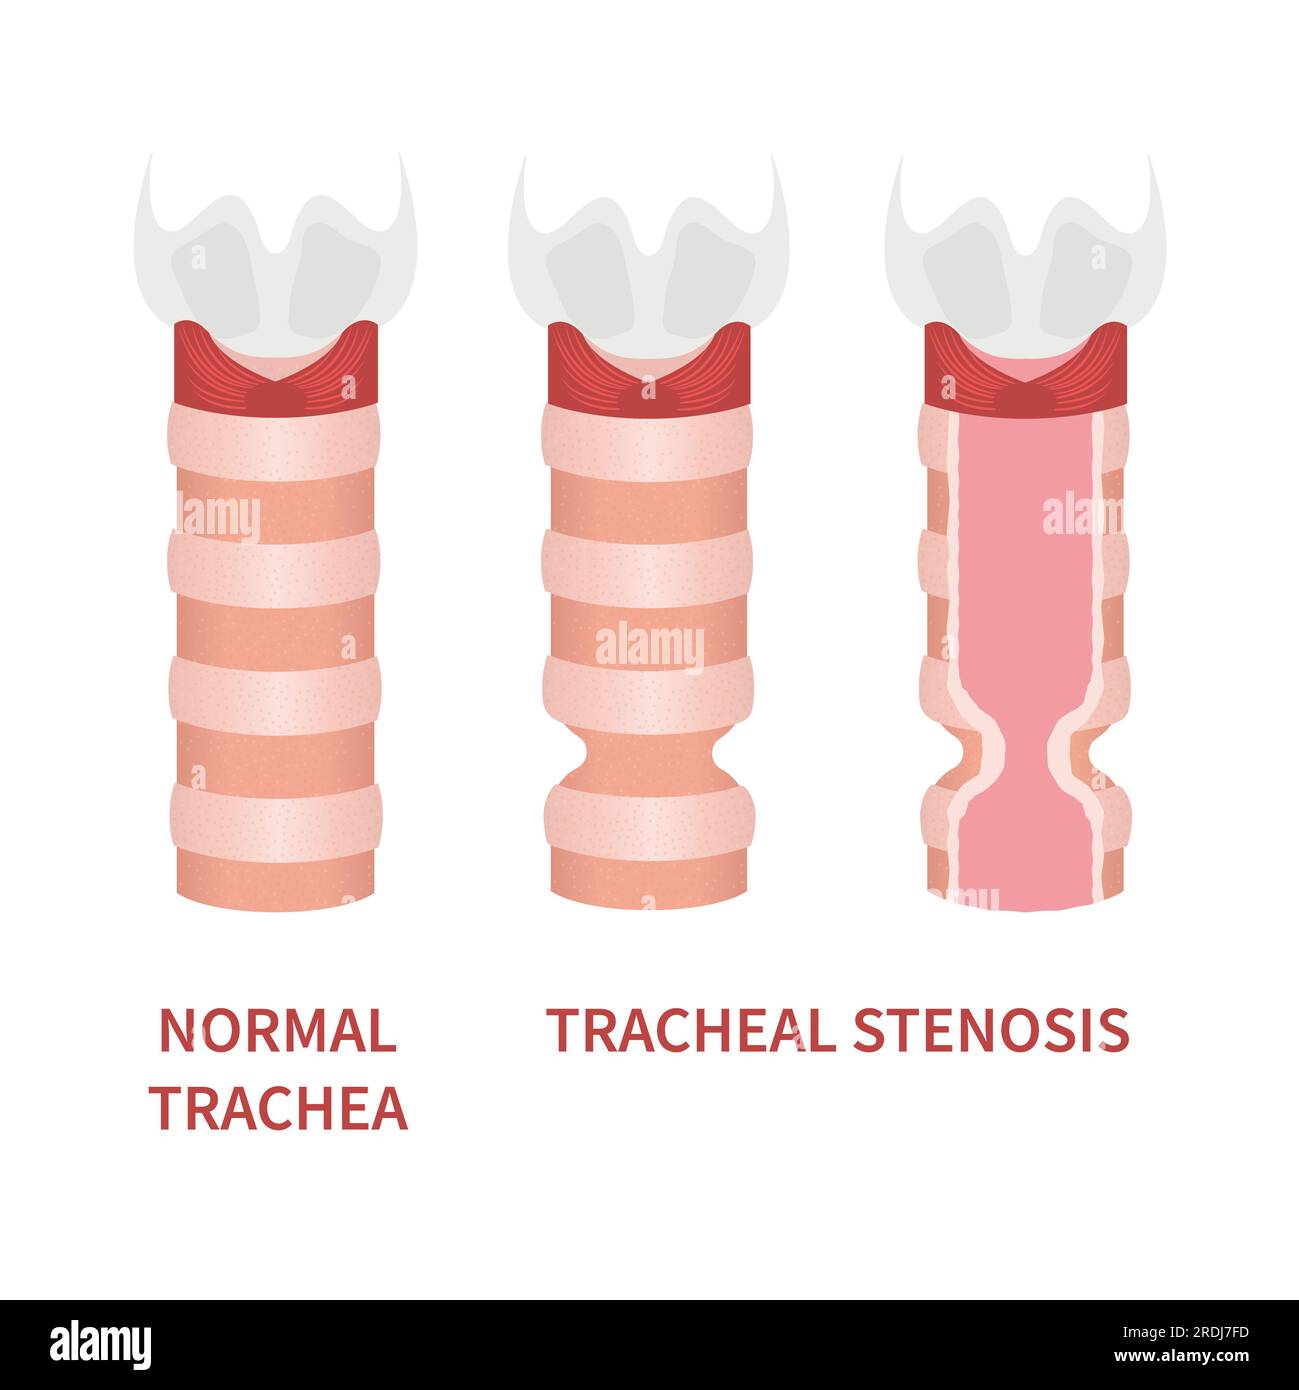

Tracheal stenosis, illustration Stock Photohttps://www.alamy.com/image-license-details/?v=1https://www.alamy.com/tracheal-stenosis-illustration-image559123361.html

Tracheal stenosis, illustration Stock Photohttps://www.alamy.com/image-license-details/?v=1https://www.alamy.com/tracheal-stenosis-illustration-image559123361.htmlRF2RDJ7FD–Tracheal stenosis, illustration